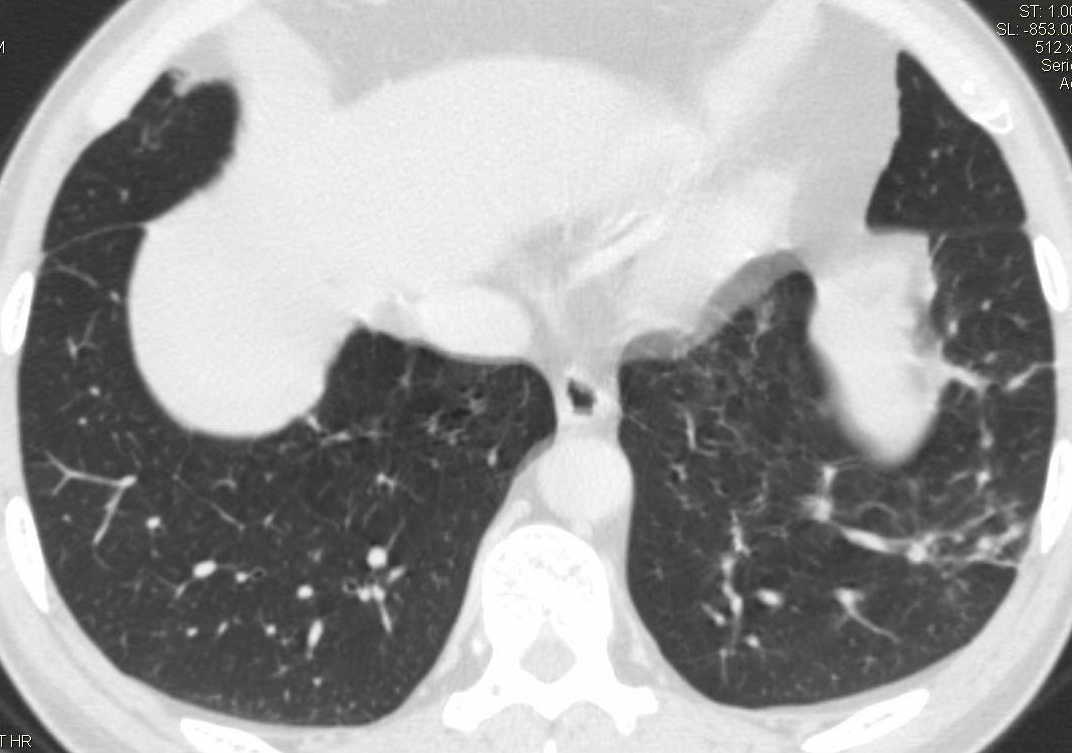

标题: CT15857:男性 58岁 咳痰带血 无发热 请各位大侠发表一下意见 [打印本页]

标题: CT15857:男性 58岁 咳痰带血 无发热 请各位大侠发表一下意见

两肺下叶肺纹理增多、增粗并呈“树芽状”改变。支气管扩张呈囊状,部分呈柱状改变。其周围可见散在的斑片样及条索样密度增高影,右肺下叶近叶间胸膜可见一形态不规则的高密度结节影,并与胸膜粘连。

考虑:支扩并发感染。

双肺多发炎性病灶,结核可能性大,建议抗炎治疗复查.右肺下叶前基底段结节灶,高度警惕肺癌可能

双肺间质性改变(间质纤维化?)伴支扩。右肺下叶有毛刺的小结节,考虑周围型肺癌可能性。